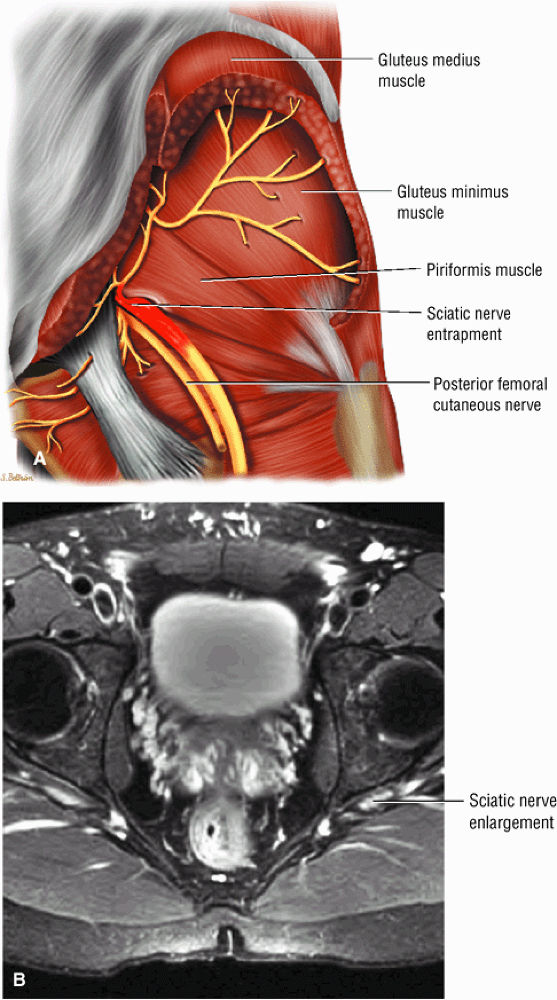

The sciatic nerve, located directly posterior to the posterior column of the acetabulum, demonstrates intermediate signal intensity. It exits the pelvis through the greater sciatic foramen (the greater sciatic foramen is bordered by the ilium, the rim of the greater sciatic notch, the sacrotuberous ligament, and the sacrospinous ligament) inferior to the piriformis muscle.

-

Entrapment of the sciatic nerve at this location may be associated with the piriformis syndrome. Asymptomatic hypertrophy of the piriformis muscle in this syndrome is best appreciated on axial images. The piriformis originates from the anterior sacrum and greater sciatic notch and inserts on the upper border of the greater trochanter. The piriformis divides the greater sciatic foramen into superior and inferior portions.

The sciatic nerve sheath contains two peripheral nerves: the tibial and common peroneal nerves.

The sciatic nerve (Fig. 3.70) is composed of the upper sacral plexus roots from the anterior and posterior divisions of L4, L5, S1, S2, and S3. The two peripheral nerves, the tibial (anterior divisions) and the common peroneal (posterior divisions), are contained within the same connective tissue sheath as the sciatic nerve.